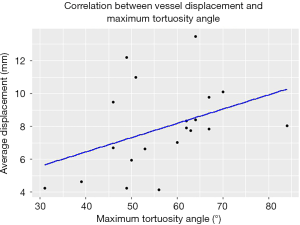

The median maximum tortuosity angle of the aortoiliac segment was 58° (range, 31°–84°). A moderate monotonic relationship (Spearman’s ρ=0.45, P<0.05) was found between the extend of vessel displacement and the maximum tortuosity angle of the aortoiliac segment. The scatterplot is provided in Figure 6.